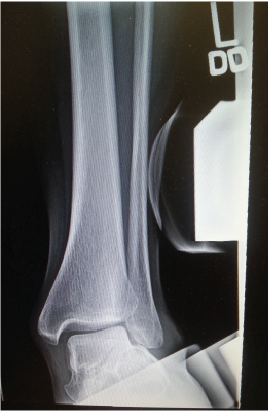

In 1996, Myerson recognized the presence of deltoid ligament failure in late stage adult-acquired flatfoot deformity and added a fourth stage to the original classification.2 This is visible on a weightbearing AP X-ray by valgus tilt of the talus within the ankle mortise and is associated with deltoid insufficiency.

Preoperative imaging of the stage III adult-acquired flatfoot is necessary to assess the deltoid ligamentous structures. This should include weightbearing radiographs of the foot and ankle as well as magnetic resonance imaging (MRI) or diagnostic ultrasound. Weightbearing views of the ankle are necessary to evaluate the presence of valgus deformity and degenerative changes while long leg calcaneal axial and hindfoot alignment views provide information regarding frontal plane alignment. The most important angles to assess for ligamentous injury are the calcaneal pitch angle, Meary’s angle and abnormal talonavicular coverage.16